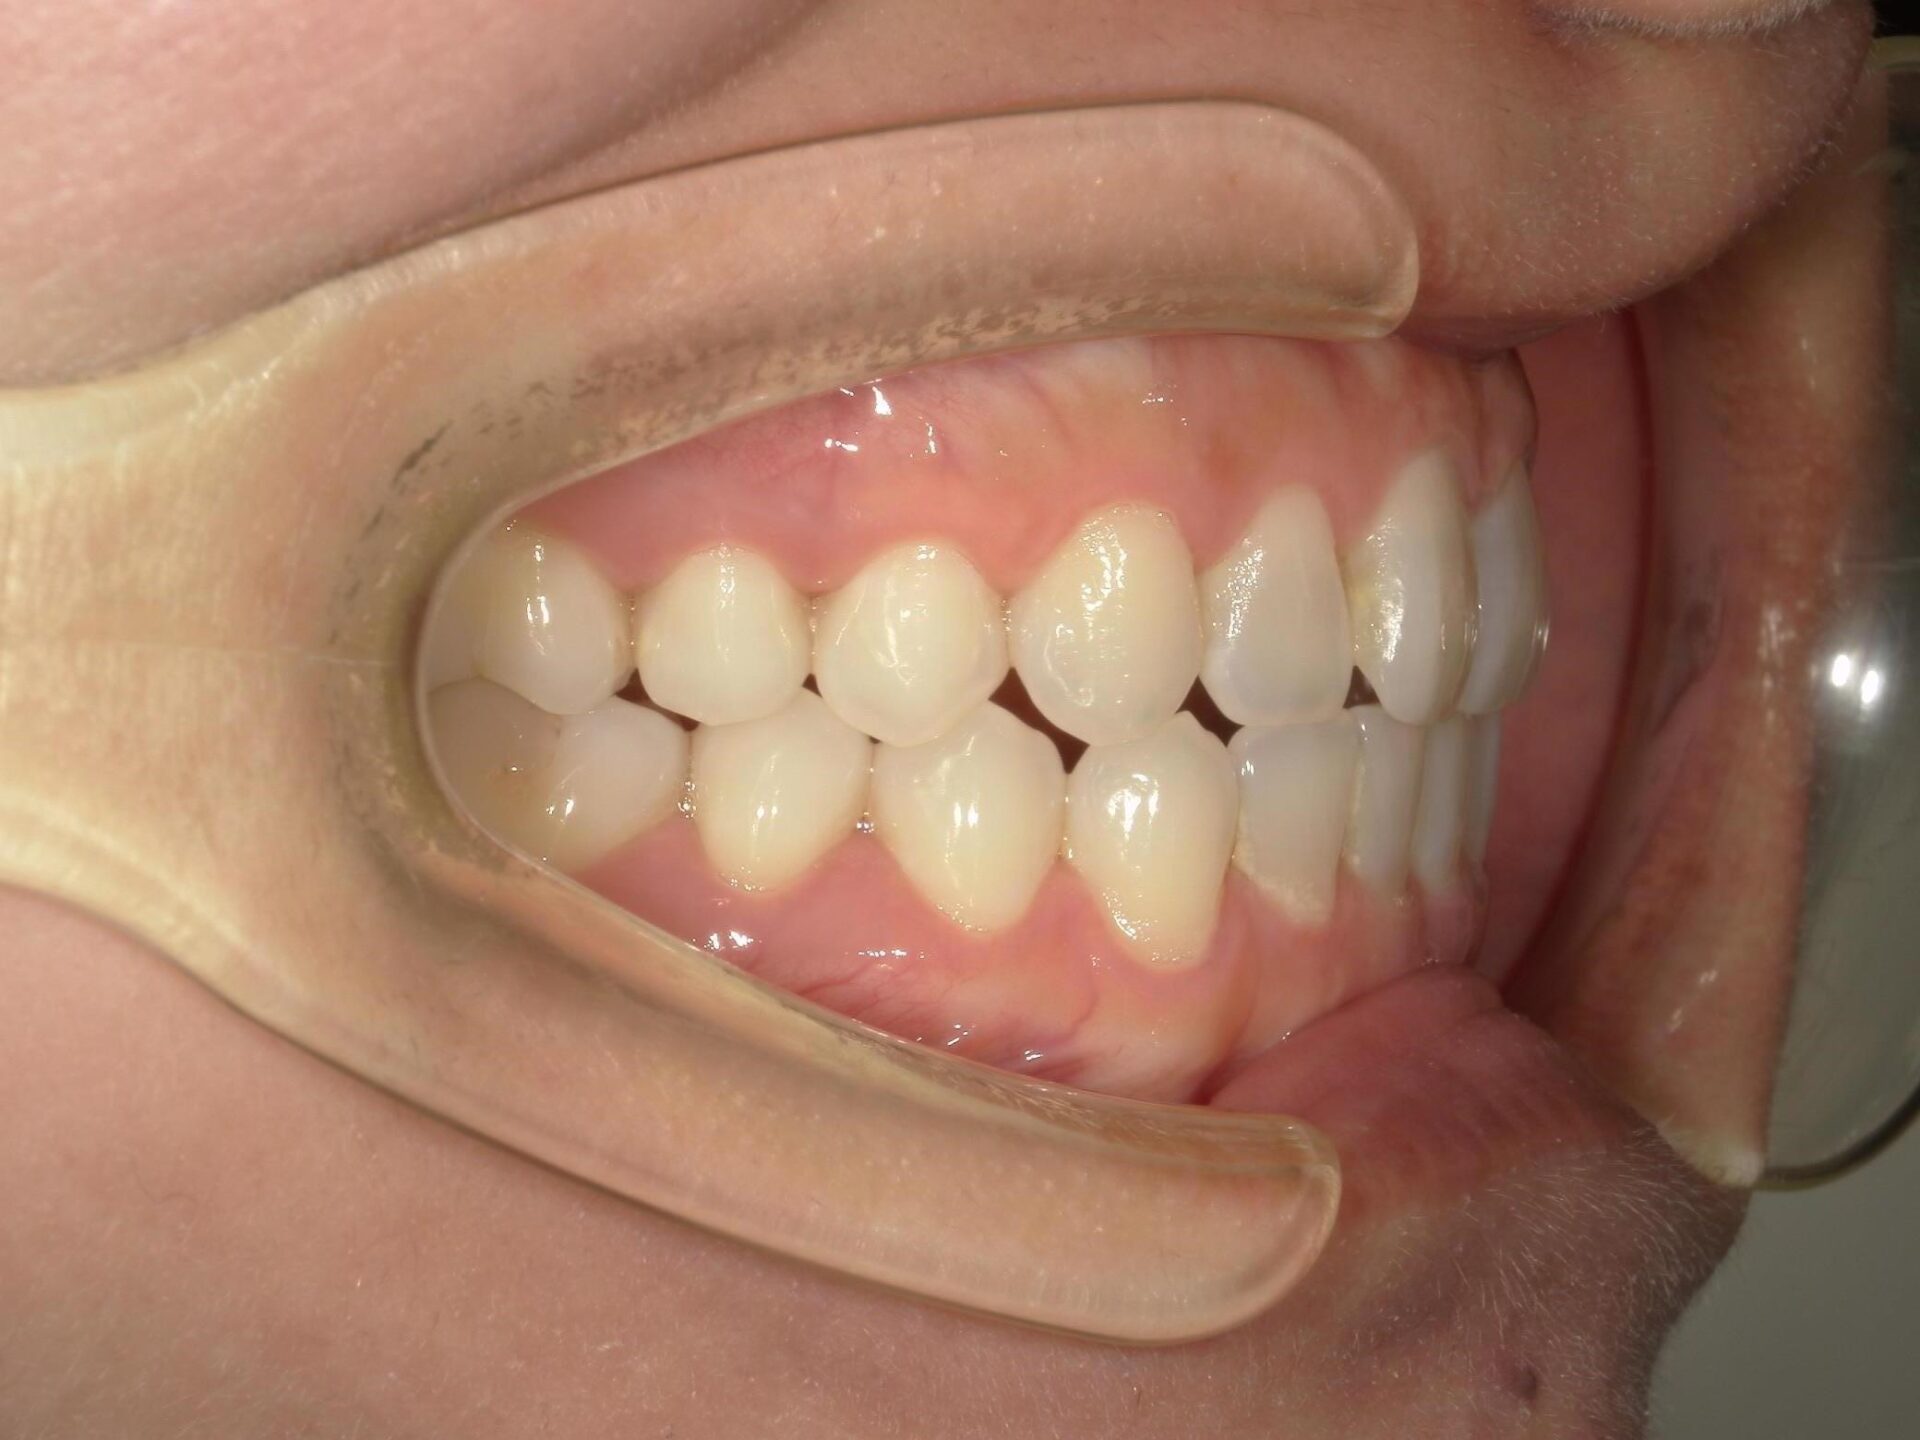

20代、男性、ワイヤー

| 施術内容 | 主訴:でこぼこで食べ物がよく挟まる。虫歯や歯肉炎に悩まされてきた。 詳細:ワイヤー矯正での歯並び改善 とても磨きやすくなったと満足されてます。 |

| 治療期間 | 16ヶ月(2/3現在 治療終了) |

| 費用 | ワイヤー矯正 60万円(税込660,000円) |